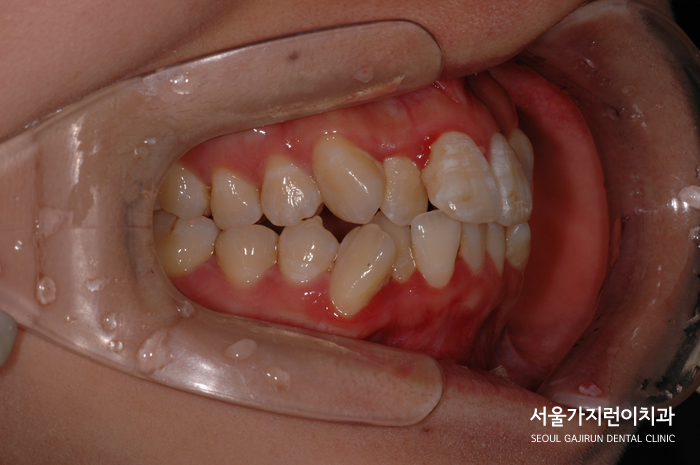

환자 분의 경우 덧니 양상이 명확히 나타난 케이스로 치아의 크기 대비 공간이 부족해 덧니화 된 경우인데요. 치아 배열이 상당히 흐트러진 경우로 정중선이 어긋나 있고 송곳니에서부터 불규칙한 교합 관계가 보여 상악 치아가 앞으로 쏠려 있는 기울어짐을 확인할 수 있었어요. 이렇게 되면 입술도 앞으로 밀려나와 돌출입처럼 보이게 되는데요. 때문에 치열을 바로 잡고 입술의 위치가 자연스럽게 뒤로 들어갈 수 있도록 돌출된 입도 교합을 찾을 필요가 있었어요.